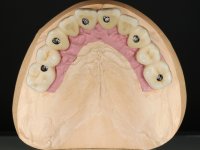

Realizada uma TAC, foi planificada a colocação de 6 implantes no maxilar superior. Foi decidida a colocação de dois implantes na zona dos incisivos centrais, dois implantes na zona dos caninos e dois na zona dos segundos pré-molares. A ausência de estrutura óssea na zona distal do primeiro quadrante implicava a realização de uma regeneração óssea no seio maxilar direito. A cirurgia foi realizada e após a colocação dos implantes foi feita a impressão para confeção de uma prótese provisória metalo-acrílica aparafusada para colocação em carga imediata no dia seguinte. O implante colocado na zona do seio maxilar direito não foi colocado em carga. Passados 6 meses foi realizada a impressão aos 6 implantes com técnica de moldeira aberta e foram confecionados os modelos de trabalho. Numa consulta seguinte foram montados os modelos de trabalho em articulador semi-ajustável utilizando o arco facial e a relação inter-maxilar obtida com a prótese provisória. Foi feita uma muralha de silicone sobre a ponte provisória com o objetivo de orientar o trabalho laboratorial. Realizada a infra estrutura metálica aparafusada esta foi provada em boca e finalmente após colocação de cerâmica o trabalho foi colocado definitivamente. Como passaram vários meses após a realização da primeira TAC foi feita uma segunda para planificar a colocação de implantes no 4º quadrante. Colocaram-se 3 implantes na mesma sessão em que foi feita a extração dos pilares da ponte. Estes implantes foram posteriormente reabilitados com uma ponte metalo-cerâmica aparafusada de três elementos.